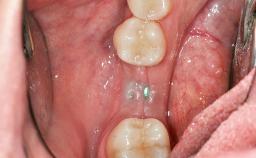

In 1983, a 51-year-old non-smoking patient was referred for the treatment of moderate chronic periodontitis. At the initial examination, 47% of sites exhibited probing depths of 4 to 6 mm. Periodontal therapy consisted of initial periodontal treatment including oral-hygiene instructions and supra- and subgingival debridement, followed by periodontal surgery to eliminate residual pockets.

| Soft Tissue Grafting | Simultaneous |